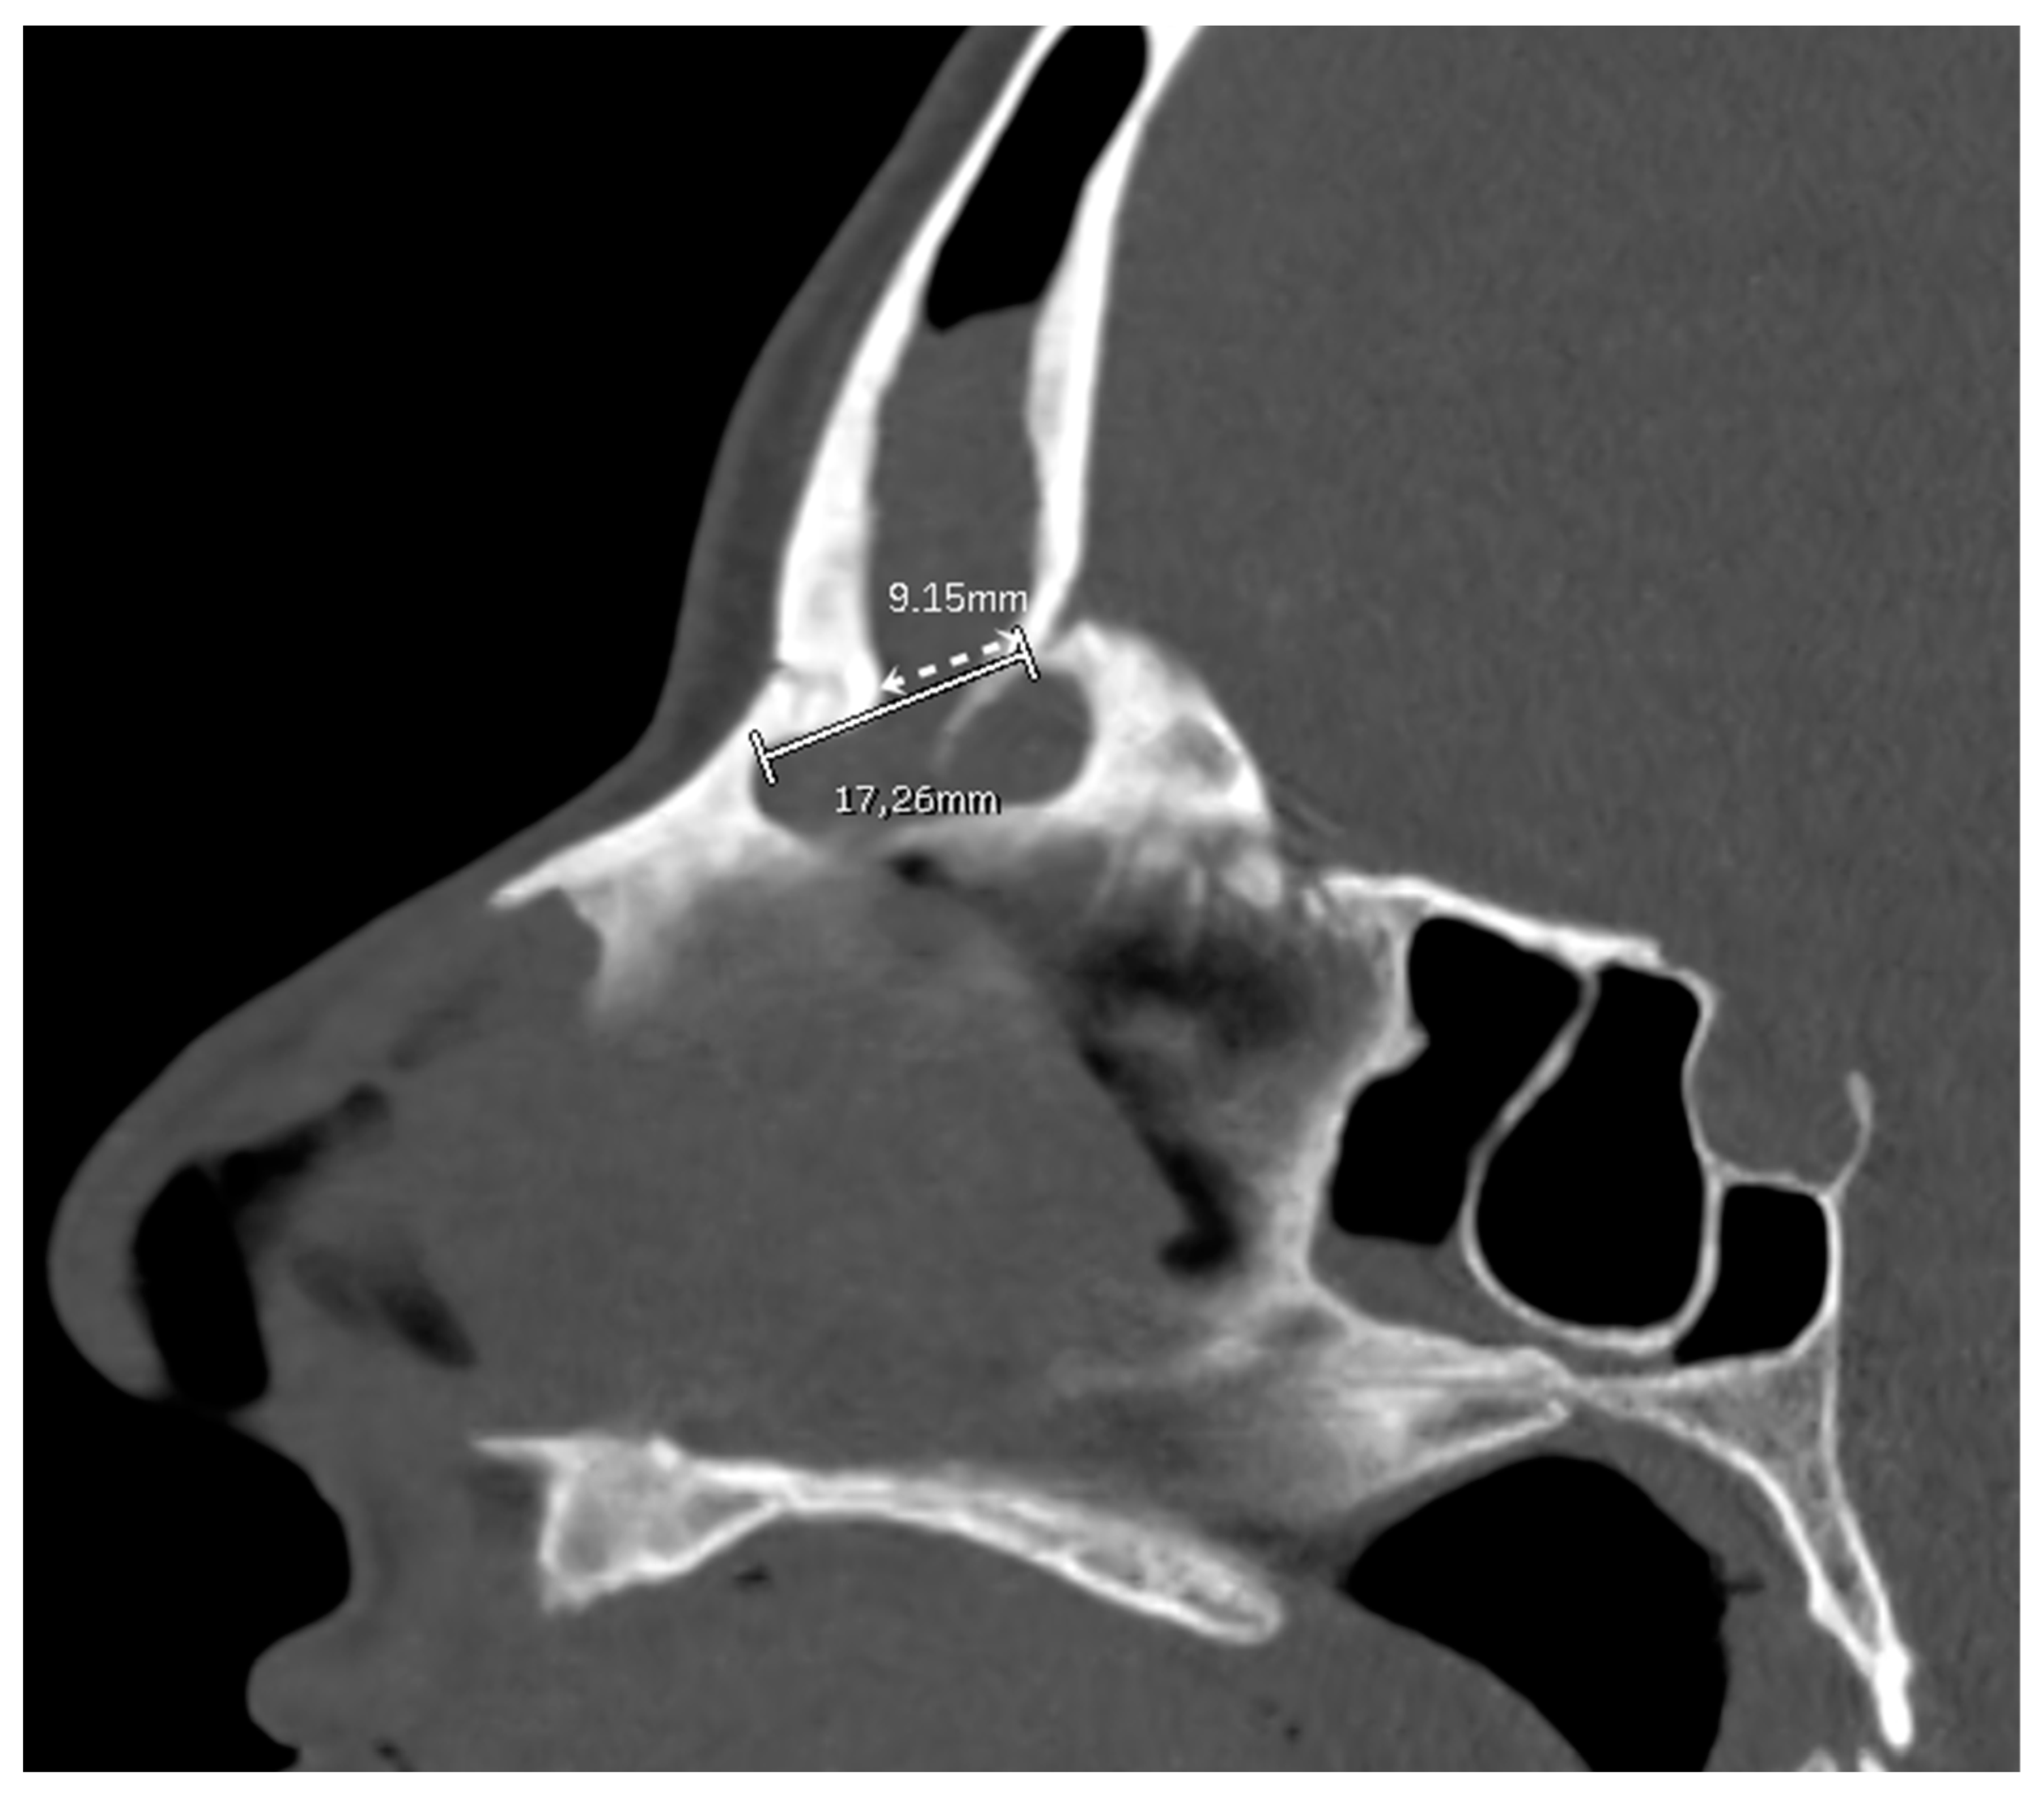

The FOAP min was measured as the distance between the posterior edge of the frontal beak and the posterior wall of the frontal sinus, following the indications of the previously mentioned article (Figure 3).

Figure 3. A patient undergoing a DRAF III for bilateral fronto-ethmoidal rhinosinusitis. On the pre-operative sagittal CT scan, the FOAP min (dashed white line with arrows) is measured as the distance between the posterior edge of the frontal beak and the posterior wall of the frontal sinus. The solid white line corresponds to the FOAP max.

High-resolution CT images were analyzed from all the patients included by two authors (C.C. and M.B.). Mid-sagittal images, identified by the location of the nasal septum and crista galli, were chosen for analysis and measurement. The minimum and maximum frontal sinus outflow anteroposterior diameters (FOAP min and FOAP max, respectively) were measured. The FOAP max was measured as the sum of 1) the mid-sagittal anteroposterior thickness of the nasal beak and 2) the mid-sagittal anteroposterior distance between the nasal beak and the anterior most skull base (Figure 2), as described in the study by Zhang et al. It corresponds to the distance between the nasion and the posterior wall of the frontal sinus.